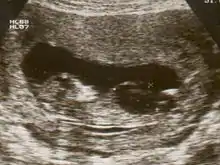

Fetal megacystis is diagnosed during pregnancy by ultrasound imaging procedures. Since it can be associated with genetic abnormalities, further ultrasounds and tests may be administered during pregnancy. It may also be diagnosed as megalocystis, and/or termed megabladder, which is the same condition.